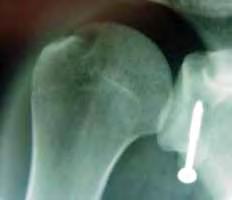

Risken att utveckla höftluxation hos barn med CP är 10-15%. Det är sedan mer än 50 år tillbaka känt att man i många fall kan förhindra uppkomsten av höftluxation med förebyggande behandling. I den förebyggande behandlingen ingår kontrakturprofylax med ortoser och bra positionering i liggande och sittande. Inte sällan krävs dessutom operation; adduktor-psoastenotomi, variserande proximal femurosteotomi och/eller bäckenosteotomi för att förhindra luxation (se Figur).

Figur 2. 5-årig pojke med CP. A. Röntgen visar lateralisering av caput i hö höft. B. Efter operation med variserande femurosteotomi.